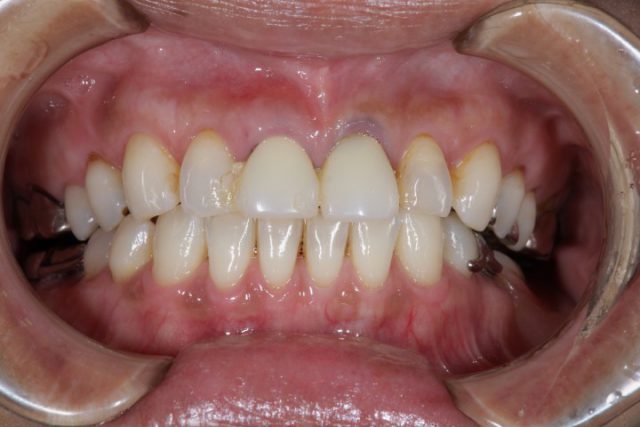

施術後

今回のように以前に施術した詰め物が変色したり、場合によっては欠損してしまったりの時に思い切ってオールセラミックによる施術を検討されてはいかがでしょうか。